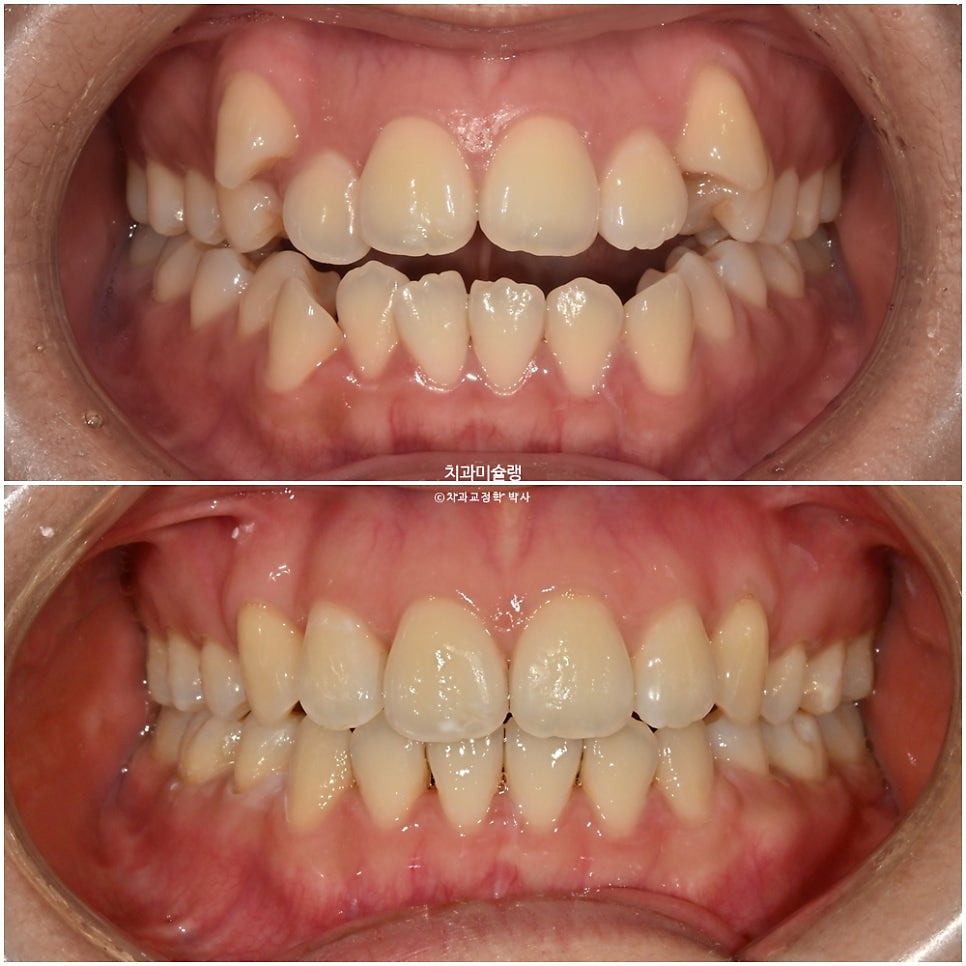

초진 시 환자 상태

2023년 9월 내원

덧니와 개방교합 때문에 오신 환자분 입니다.

덧니가 상당히 심한편입니다.

앞니뿐 아니라 작은어금니까지 또있는 개방교합입니다.

어금니 교합관계는 2급 입니다.

덧니를 제자리 시키려면 발치가 필수적인 상황입니다만

입매를 보면 하관에서 인중이 차지하는 비율이 크고 입술이 얇습니다.

치료 결과 비교

이제 전후비교 보겠습니다.

2023.09-2026.02

유지장치까지 잘 들어간 모습입니다.

치료 전반에 걸쳐 치간삭제는 하지 않았습니다.

송곳니 덧니 때문에 윗입술 양측이 들려있던 부분이 개선되었습니다.

아랫입술은 소량 뒤로 들어갔고 윗입술은 거의 처음 그대로 유지되었습니다.